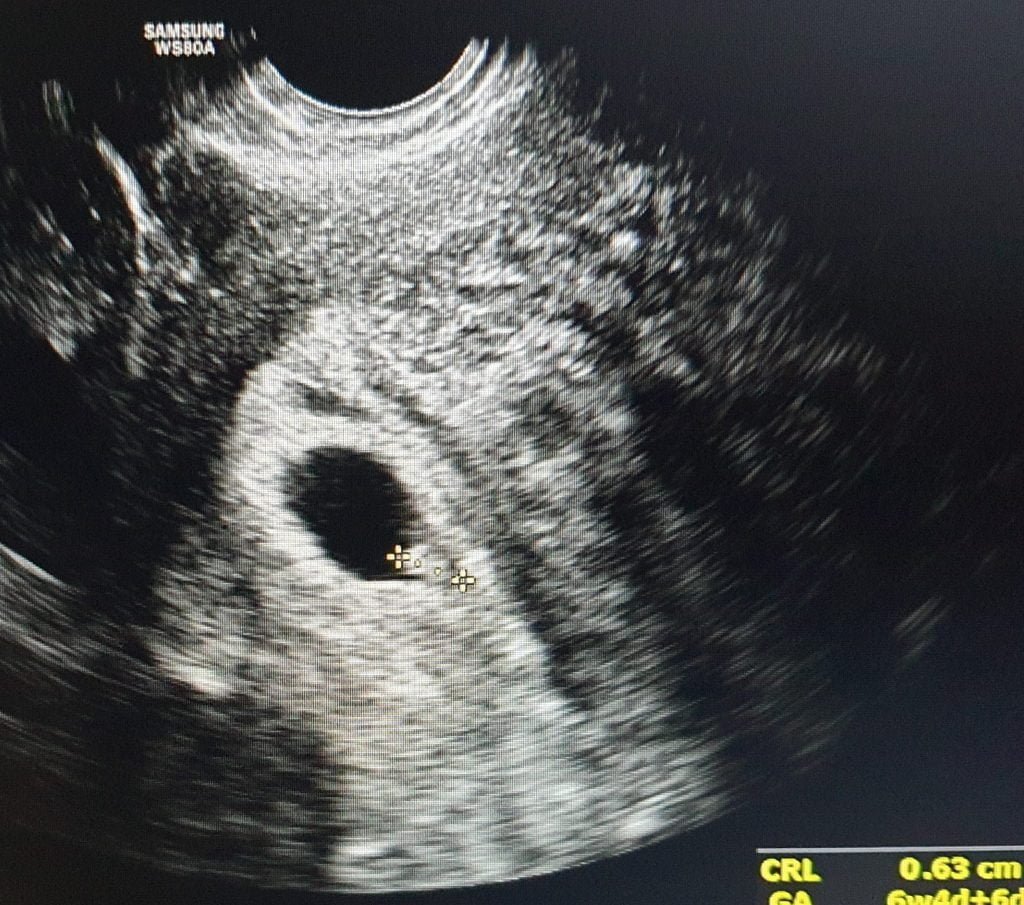

Ecografia endovaginala este o investigatie nedureroasa folosita in obstetrica si ginecologie. Nu iradiaza (se folosesc ultrasunete). Evidentiza starea uterului, trompelor, ovarele si cervixul.

Ecografia este o metodă neiradiantă, pe bază de ultrasunete, prin care se vizualizează diferite structuri anatomice.

Ecografia este o metodă neiradiantă, pe bază de ultrasunete, prin care se vizualizează diferite structuri anatomice. Ultrasunetele sunt inofensive pentru organele analizate.

Ecografia 3D/4D, este o investigatie bazata pe ultrasunete care este folosita frecvent in obstetrica. Este superioara ecografiei 2D

Ecografia 5D aduce in plus o deosebita acuratete a detaliilor, acuratete obtinuta datorita tehnologiilor de ultima ora.